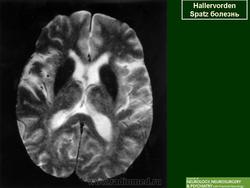

Галлервордена - Шпатца болезнь (J. Hallervorden, 1882-1965, нем. невропатолог; H. Spatz, совр. нем. невропатолог; син. ригидность прогрессирующая) - наследственная болезнь, связанная с нарушением обмена железа и липидов, проявляющаяся в возрасте 7-9 лет повышением мышечного тонуса, гиперкинезами, прогрессирующей деменцией, снижением зрения и пигментным ретинитом; наследуется по аутосомно-рецессивному типу.

Болезнь Галлервордена - Шпатца - наследственное заболевание экстрапирамидной системы, связанная с нарушением обмена железа и липидов и повреждением бледного шара и черной субстанции. Тип наследования аутосомно-рецессивный. При патоморфологическом исследовании характерным признаком является гиперпигментация бледного шара и черной субстанции. Обнаруживается пигментация коры полушарий большого мозга и таламуса. Пигмент находится внутри невронов и глиальных клеток, расположенных около сосудов; содержит железо (вместе с тем каких-либо нарушений обмена железа в организме не обнаружено). Наблюдаются утолщение и фрагментация аксонцилиндров в пораженных областях. Постепенно наступает дегенерация невронов коры полушарий большого мозга и мозжечка. Характеризуются нарастающей экстрапирамидной ригидностью, гиперкинезами (атетоз, торсионная дистония), затем развивается акинетико-ригидный синдром, пирамидная микросимптоматика, снижение интеллекта. Течение медленно прогрессирующее на протяжении 10 - 20 лет.

"Глаз тигра"-наглядно и красиво.